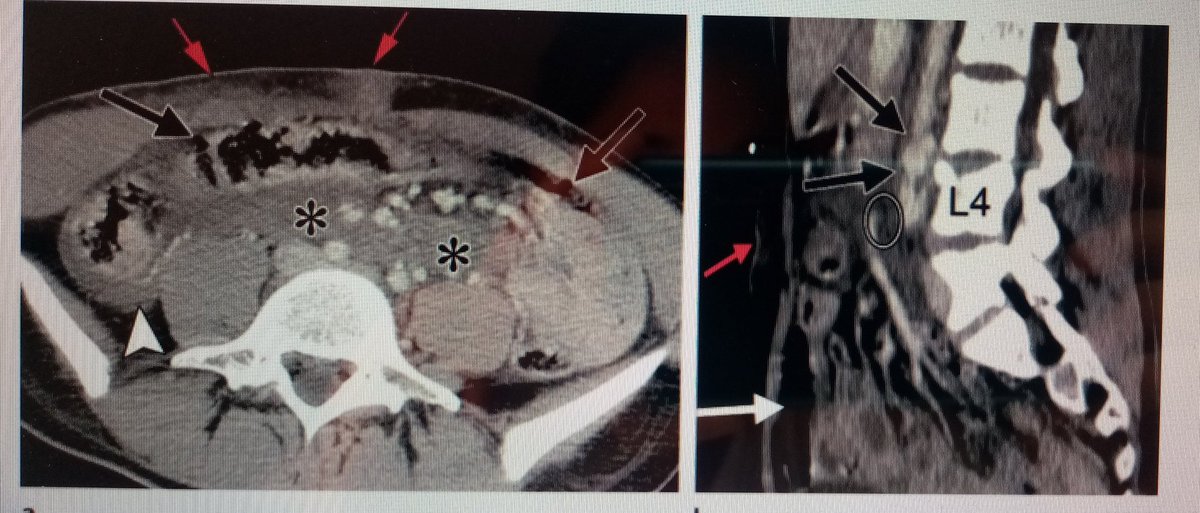

🔴LESIÓN POR CINTURÓN . Busca estigmas en piel (cuello, torso y pelvis), lesión musculatura abdominal, lesión mesenterica, lesion esternal u de troncos supraaorticos, lesión aorta dorsolumbar y lesión raquídea dorsolumbar.